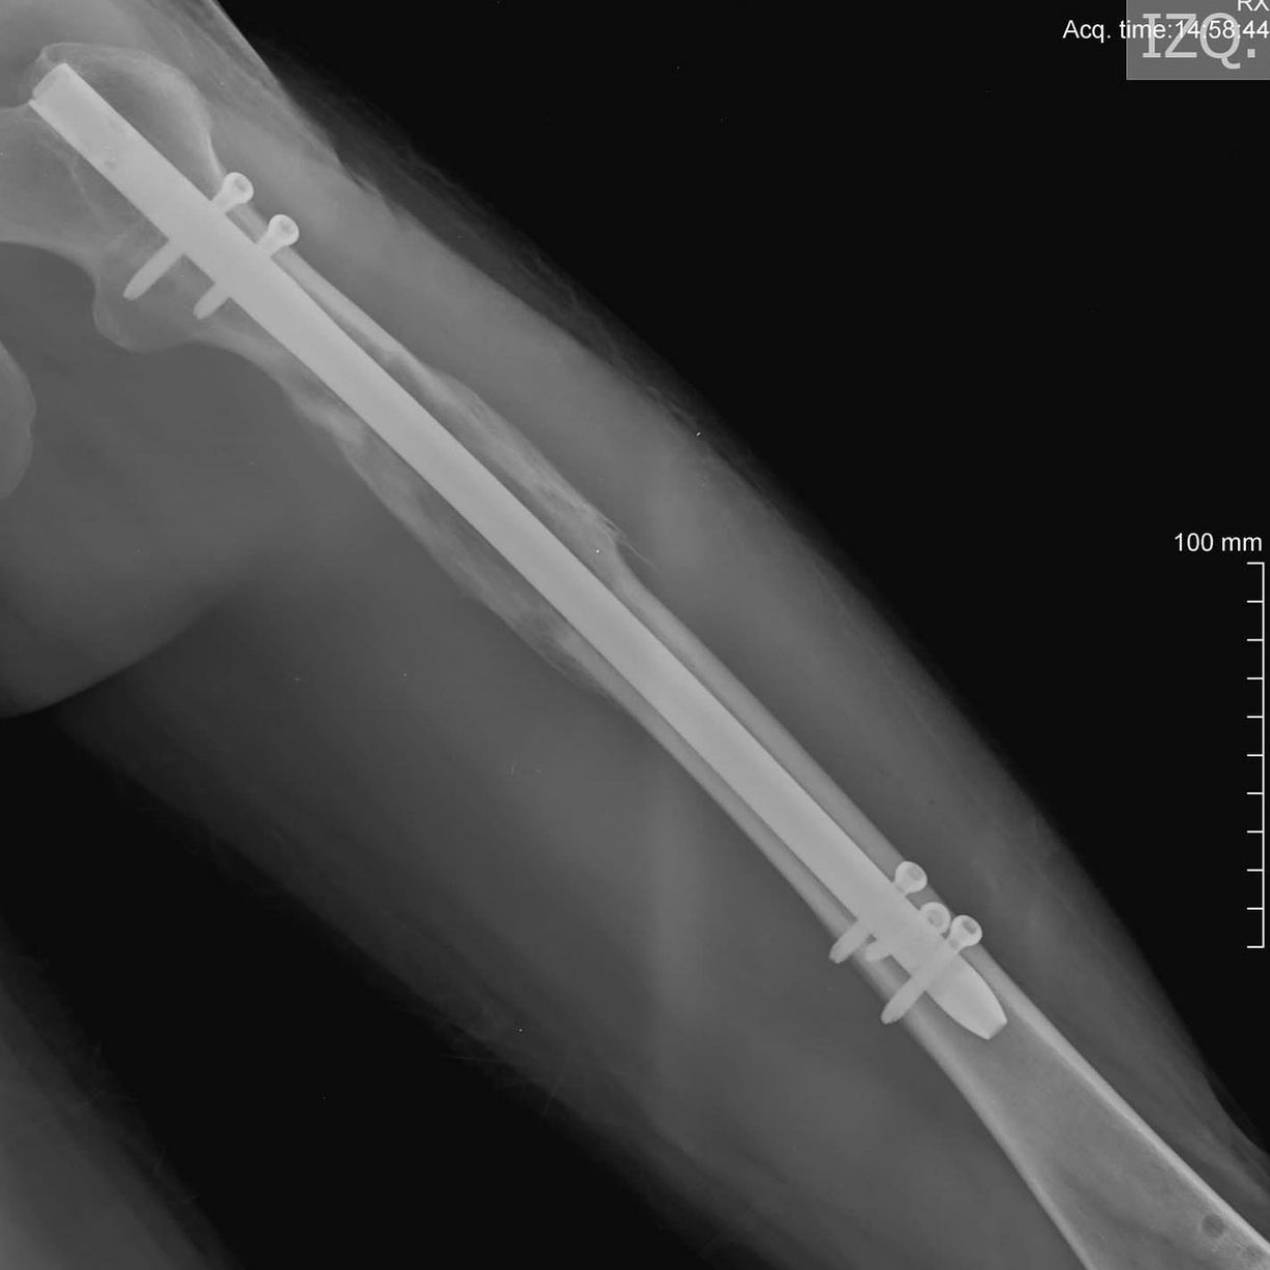

股骨肢体延长手术动画